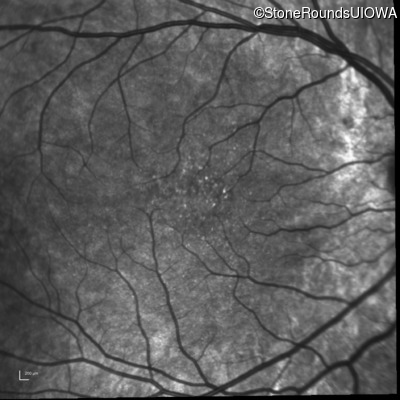

Infrared Fundus Photograph - Right - 10/16 sc

Exemplar